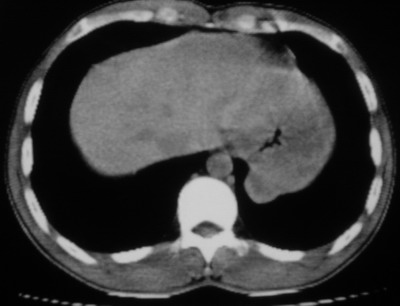

以下是引用余辉在2007-6-16 20:47:00的发言:[br]图像不边续,1左肺下叶膈后囊性病灶,与胃有密切联系,考虑局限性膈膨隆,不排除其他如脓肿等;2左膈肌脚增厚,其前方肝胃间隙内可见球形病灶,左肾上腺病变?进一步检查

以下是引用xulianj在2007-6-16 21:14:00的发言:[br]左膈肌脚增厚,支持膈肌角病变。

以下是引用卜一在2007-6-17 4:50:00的发言:[br]左膈肌脚增厚,支持膈肌角病变。